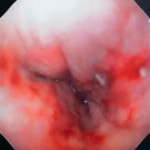

症例:炎症性ポリープ M.ダックス 10歳 オス

主訴:8ヶ月前から便が細くなり、血が混じることがある。その他、元気・食欲等、一般状態は良好。

経過:超音波検査にて直腸壁の肥厚(5㎜)が認められた。また、直腸検査で直腸全周に結節状病変を触知し、出血も確認された。消炎剤、抗生剤、整腸剤による治療への反応が長期的に悪いため、生検も含めた内視鏡検査を実施した。

内視鏡検査:肛門付近の直腸全周に、炎症および出血を伴う結節状病変を多数認めた。

病理検査:直腸の病変は、良性の非腫瘍性病変の一つである“炎症性ポリープ”と診断された。

診断後経過:炎症性ポリープは多発する傾向や腫瘍に転化する可能性があるため、消炎剤、抗生剤、整腸剤による内科療法を継続しながら、現在プルスルー法による外科的摘出術を検討中。